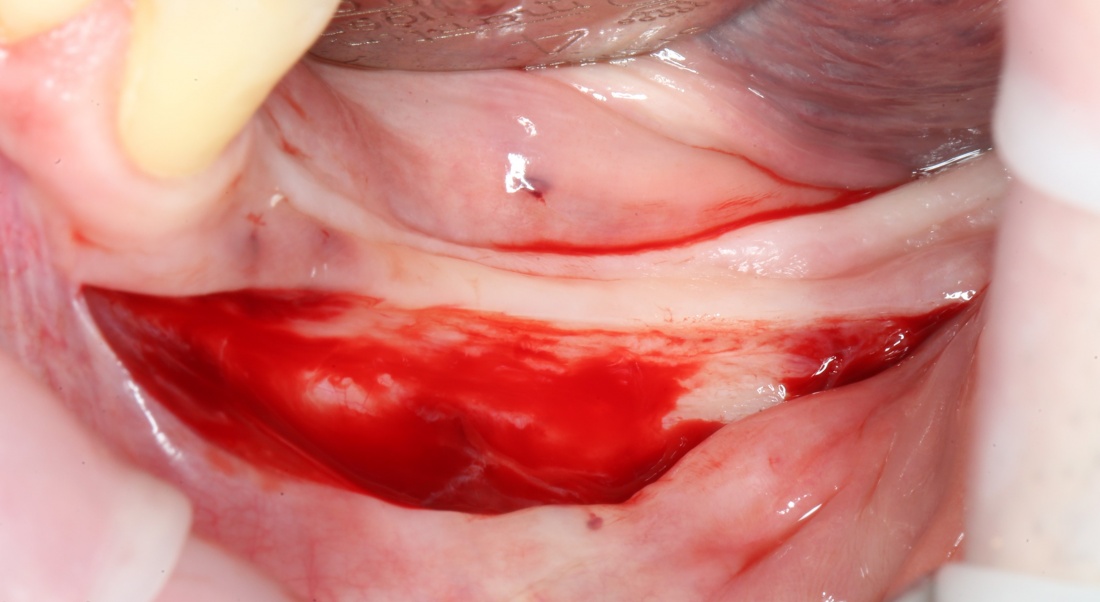

При горизонтальной остеотомии (вертикальной аугментации) очень удобен вестибулярный разрез по переходной складке или чуть ниже:

При вертикальной остеотомии (горизонтальной аугментации), наоборот, разрез делается по вершине альвеолярного гребня. При этом, «послабляющие» дополнительные разрезы не нужны.